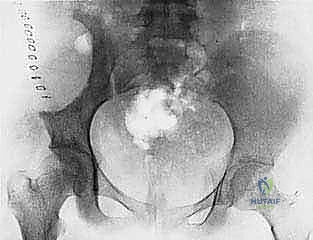

- Plain Radiography (FIG 2): While of limited value for early lesions, it provides an initial overview. As you can see in Figure 2A, we have a large lytic lesion of the right periacetabular region. Figure 2C shows a cartilage-forming lesion in the left ilium. However, plain films often underestimate the true extent of these tumors.